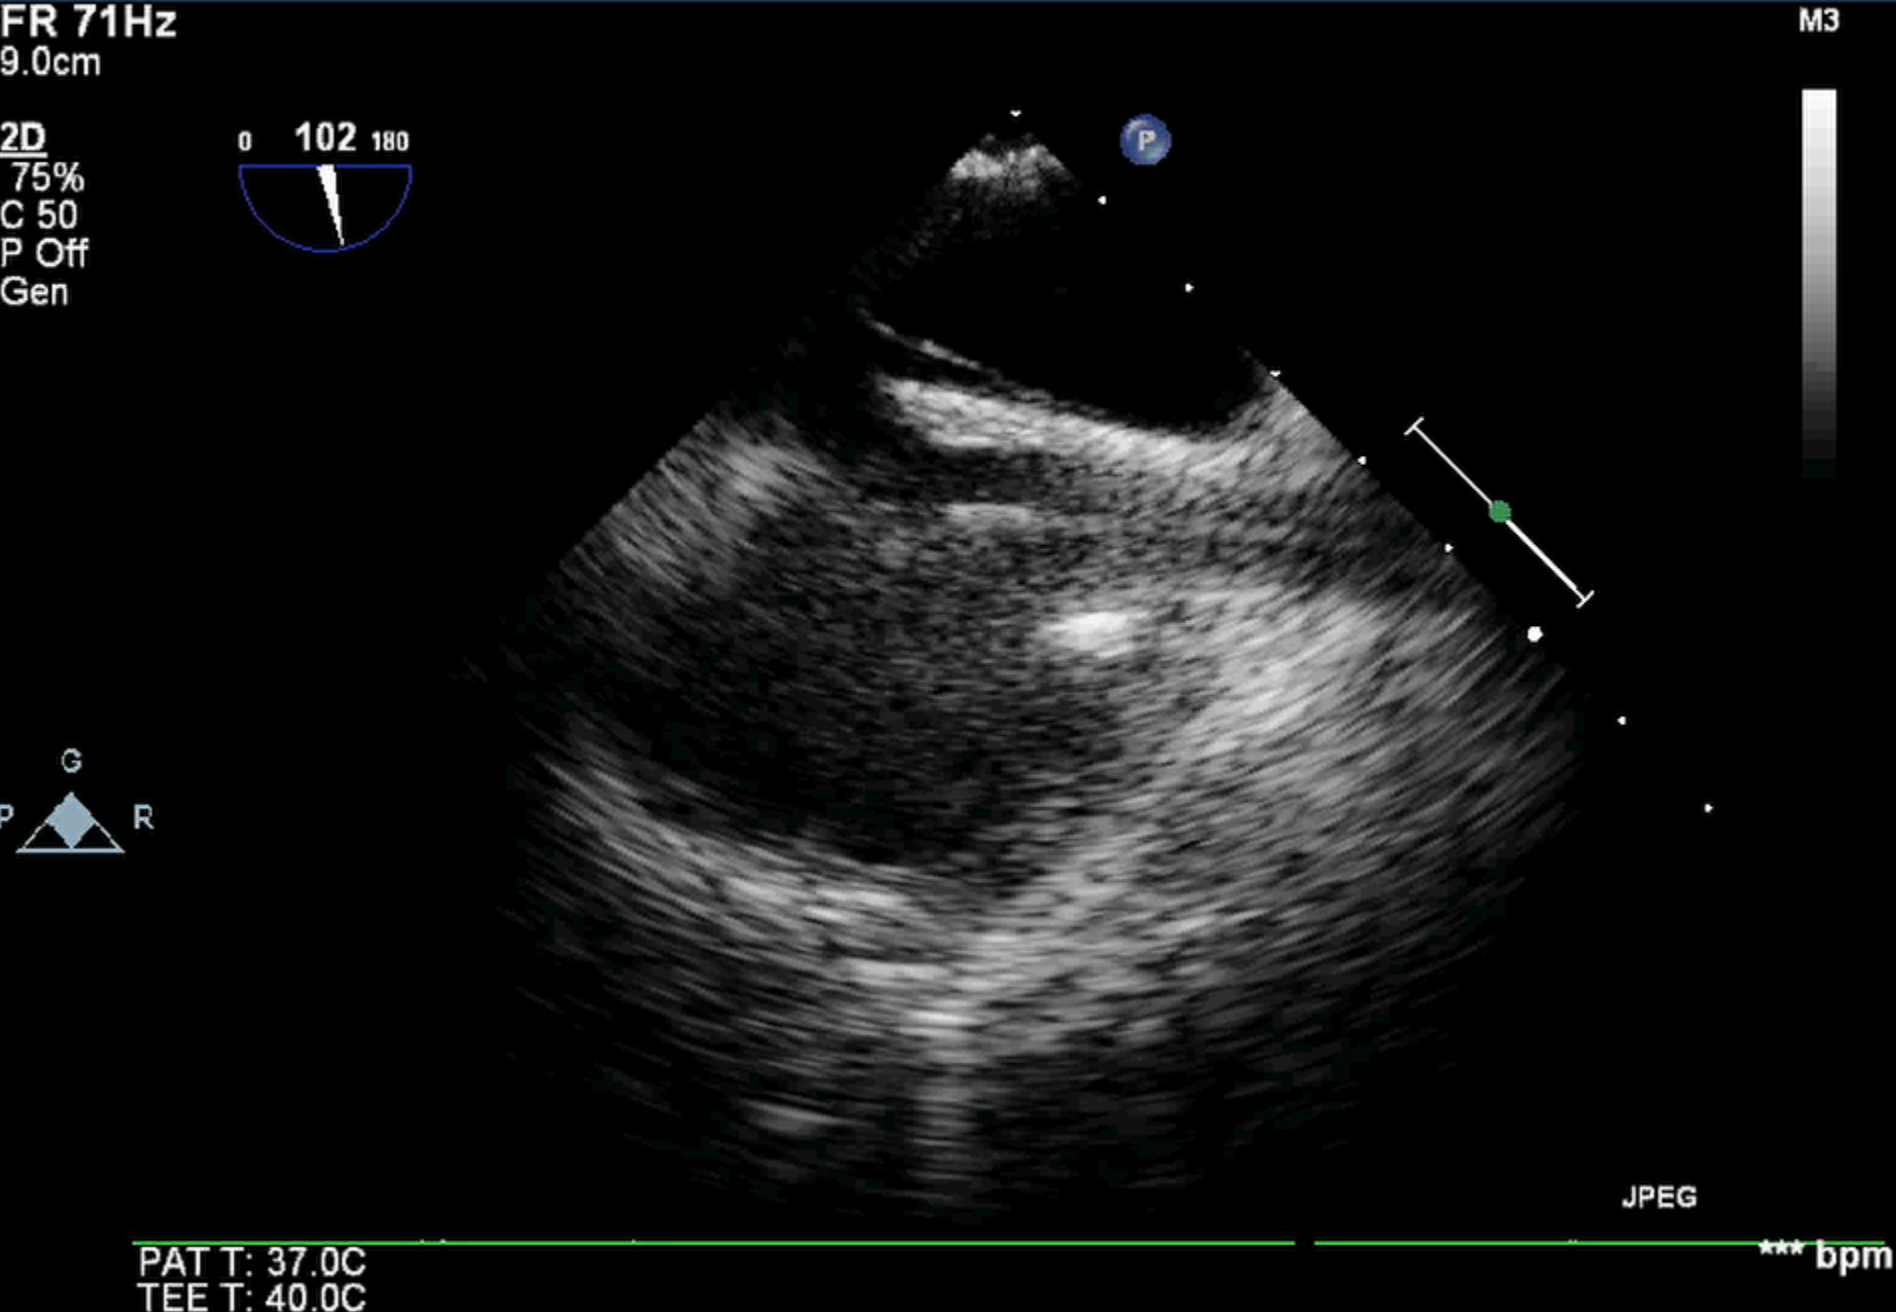

治疗上予以补液、扩容,泵入去甲肾上腺素、间羟胺稳定循环,美罗培南+替考拉宁加强抗感染,祛痰、舒张气道,镇静、镇痛,肺复张、俯卧位通气等治疗; 患者病情进行性恶化,收缩压波动在60~70 mmHg(1 mmHg=0.133 kPa),SpO2波动在70%~80%左右,PaO2最低49 mmHg。11月25日22:40右侧股静脉、股动脉穿刺置管,行静脉-动脉体外膜肺氧(venous-arterial extracorporeal membrane oxygenation, VA-ECMO)治疗(ECMO参数:转速2 300 r/min,血流量3 L/min,氧流量4 L/min,氧浓度1.0),患者血压较前改善130/80 mmHg,但出现上半身发绀,右上肢SpO2 75%左右; 查右桡动脉血气:PaCO2 44 mmHg,PaO2 38 mmHg,SO2 78%; 中心静脉血氧饱和度52%; 遂充分消毒、铺巾,在经食道超声引导下增加股静脉导管置管深度,将股静脉导管尖端送至上腔静脉(图 2所示),患者右上肢SpO2由75%逐渐上升至88%,复查右桡动脉血气分析:PaCO2 46 mmHg,PaO2 55 mmHg,SO2 88%; 中心静脉血氧饱和度66%。继续予以保护肺通气(潮气量6 mL/Kg,平台压25 cmH2O)、俯卧位通气、抗感染、化痰、抗凝及营养支持等治疗; 2022-12-15复查床边胸片提示双肺感染较前好转; 调节呼吸机参数(模式V-SIMV,FiO2 0.5,RR 15次/min,VT 480 mL,PEEP 5 cmH2O),减少ECMO流量至1.5 L/min; 2 h后查右桡动脉血气分析:pH 7.44,PaCO2 46 mmHg,PaO2 98 mmHg,SO2 99%; 于2022-12-15 15:00成功撤离ECMO。患者多次床边胸片见图 3~5。

| 图 2 患者经食道超声检查图 |

该患者重症肺炎、感染性休克,通常使用静脉-静脉ECMO(veno-venous ECMO,VV-ECMO)治疗改善全身氧合情况; 但患者顽固性低血压,经充分液体复苏及大剂量血管活性药物持续泵入下血压仍难以维持,考虑VV-ECMO治疗可能难以改善患者循环及器官灌注情况。经综合评估,笔者采用VA-ECMO治疗,患者循环逐渐稳定,但随之出现南北综合征,本治疗团队针对肺功能情况,给予深镇静、镇痛,调节呼吸机参数、肺复张、俯卧位通气等治疗改善肺功能、改善上半身缺氧情况,但效果不佳; 也尝试使用β受体阻滞剂降低患者心排量,同时增加ECMO流量,使混合平面更接近升主动脉,但效果亦不理想。针对此种情况,笔者也考虑更换ECMO治疗模式,采用VV-ECMO或静脉-动脉-静脉ECMO(veno-arterial-venous ECMO, VAV-ECMO)治疗模式[3]。更换ECMO治疗模式,又存在更多的穿刺置管风险、出血风险以及导管感染风险。根据“差异性静脉氧回流”理论,股动-静脉置管VA-ECMO期间,下腔静脉回流的血液为富氧血流,上腔静脉回流的血液为低氧血流[4]。笔者增加股静脉导管置管深度,将股静脉导管尖端送至上腔静脉,让ECMO更多引流上腔静脉低氧血流,让下腔静脉富氧血流更多的回流至右心,从而改善了患者上半身缺氧的情况,避免了更换ECMO治疗模式。